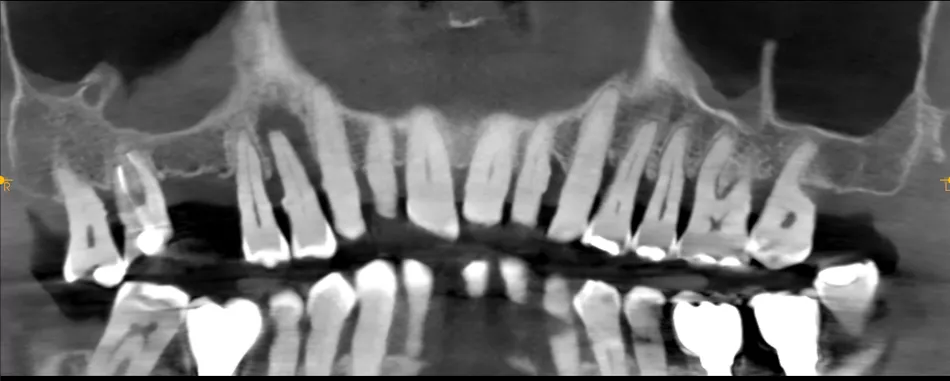

A 78-year-old male in good general health, with no medication and a negative smoking history, presented with mobility of the maxillary right second premolar (tooth 15) (Fig 1a. 1b). Clinical examination revealed severe occlusal wear, plaque accumulation, subgingival calculus, bleeding on probing, and multiple carious lesions. Periodontal assessment showed probing depths >10 mm and grade III mobility. CBCT confirmed circumferential vertical bone loss around tooth 15 and generalized periodontal involvement, indicating a hopeless prognosis and the need for extraction (Fig 1c).

1a. 1b. 1c. CBCT and panoramic views showing severe bone loss around tooth 15, confirming hopeless prognosis.